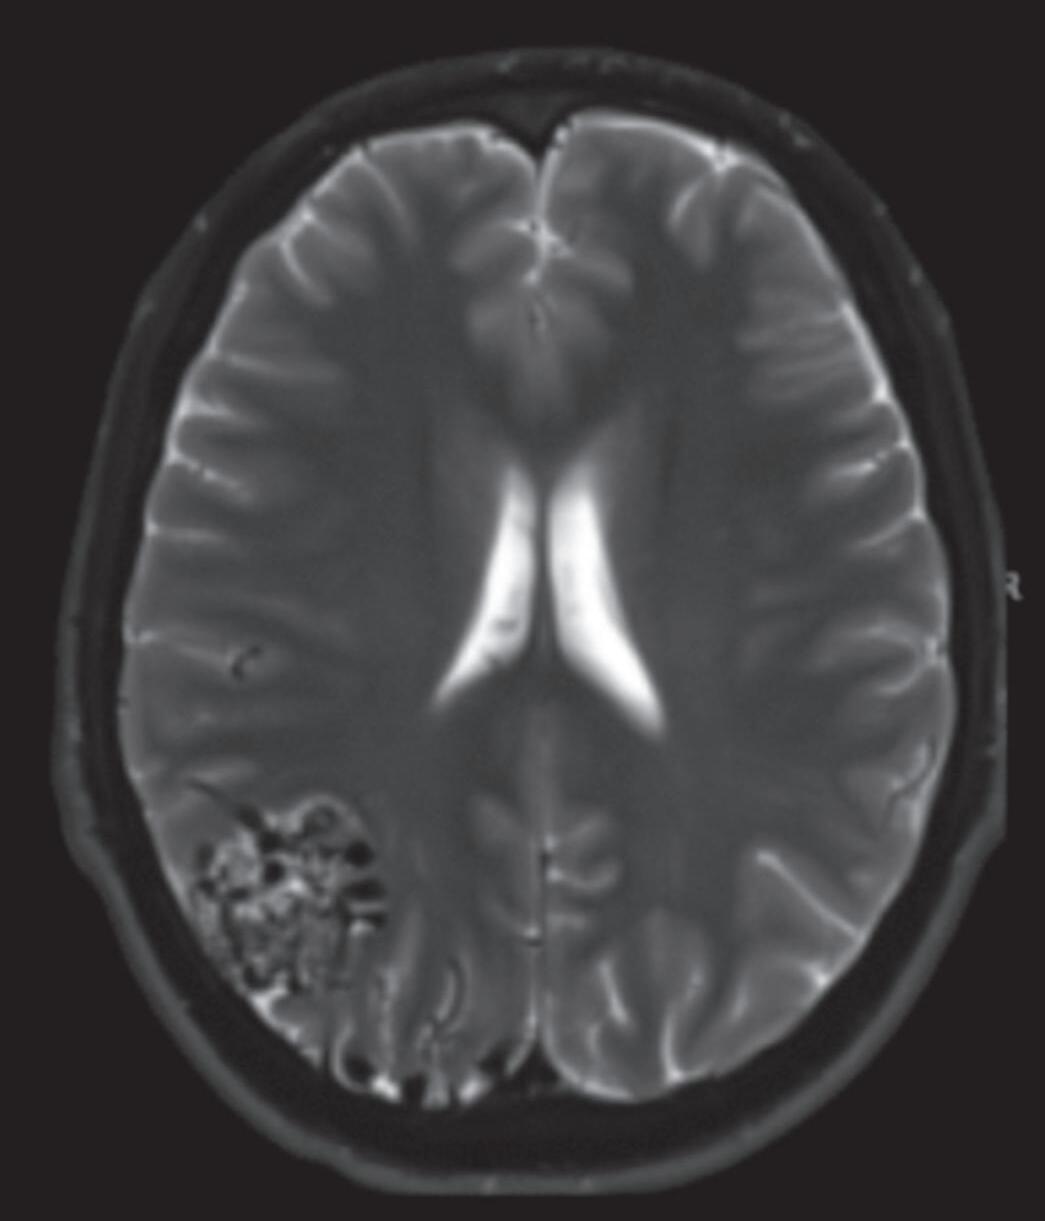

Outra classificação relacionada com a topografia divide as MAVs em: parenquimatosas, durais puras e mistas (durais e parenquimatosas). As parenquimatosas subdividem-se em: piais, subcorticais, paraventriculares (Fig. 1-10) e combinadas. Sendo que as piais, quando rompem, estão associadas mais frequentemente à hemorragia subaracnóidea e as paraventriculares associam-se ao hemoventrículo associado ou não à hidrocefalia obstrutiva.26

Fig. 1-9. RNM T2 em cortes (a) axial e (b) sagital. (c,d) Tractografia axial – sagital, demonstrando a posição de uma MAV não rota localizada na superfície basal do lobo frontal, nos giros orbitários e reto à direita (setas longas). Arteriografia digital cerebral com injeção de contraste via carótida direita, (e) AP e (f) em perfil demonstrando MAV nutrida por ramos da artéria cerebral média e cerebral anterior direita e drenagem para o seio sagital superior (seta curta).

Fig. 1-10. Ressonância magnética em corte axial (a,b) e arteriografia digital (c,d) demonstrando uma MAV pial localizada na região parieto-occipital direita, irrigada por ramos da artéria cerebral média. RNM T2 axial (e) e T1 (f) sem contraste e arteriografia cerebral (g,h) demonstrando uma MAV não rota subcortical localizada no giro pós-central esquerdo, nutrida por ramos da artéria calosomarginal e cerebral média esquerda. RNM T1 em contraste axial-sagital (a,b) e arteriografia cerebral AP-P (k,l) demonstram MAV paraventricular, localizada no átrio ventricular, nutrida por ramos da artéria cerebral média.